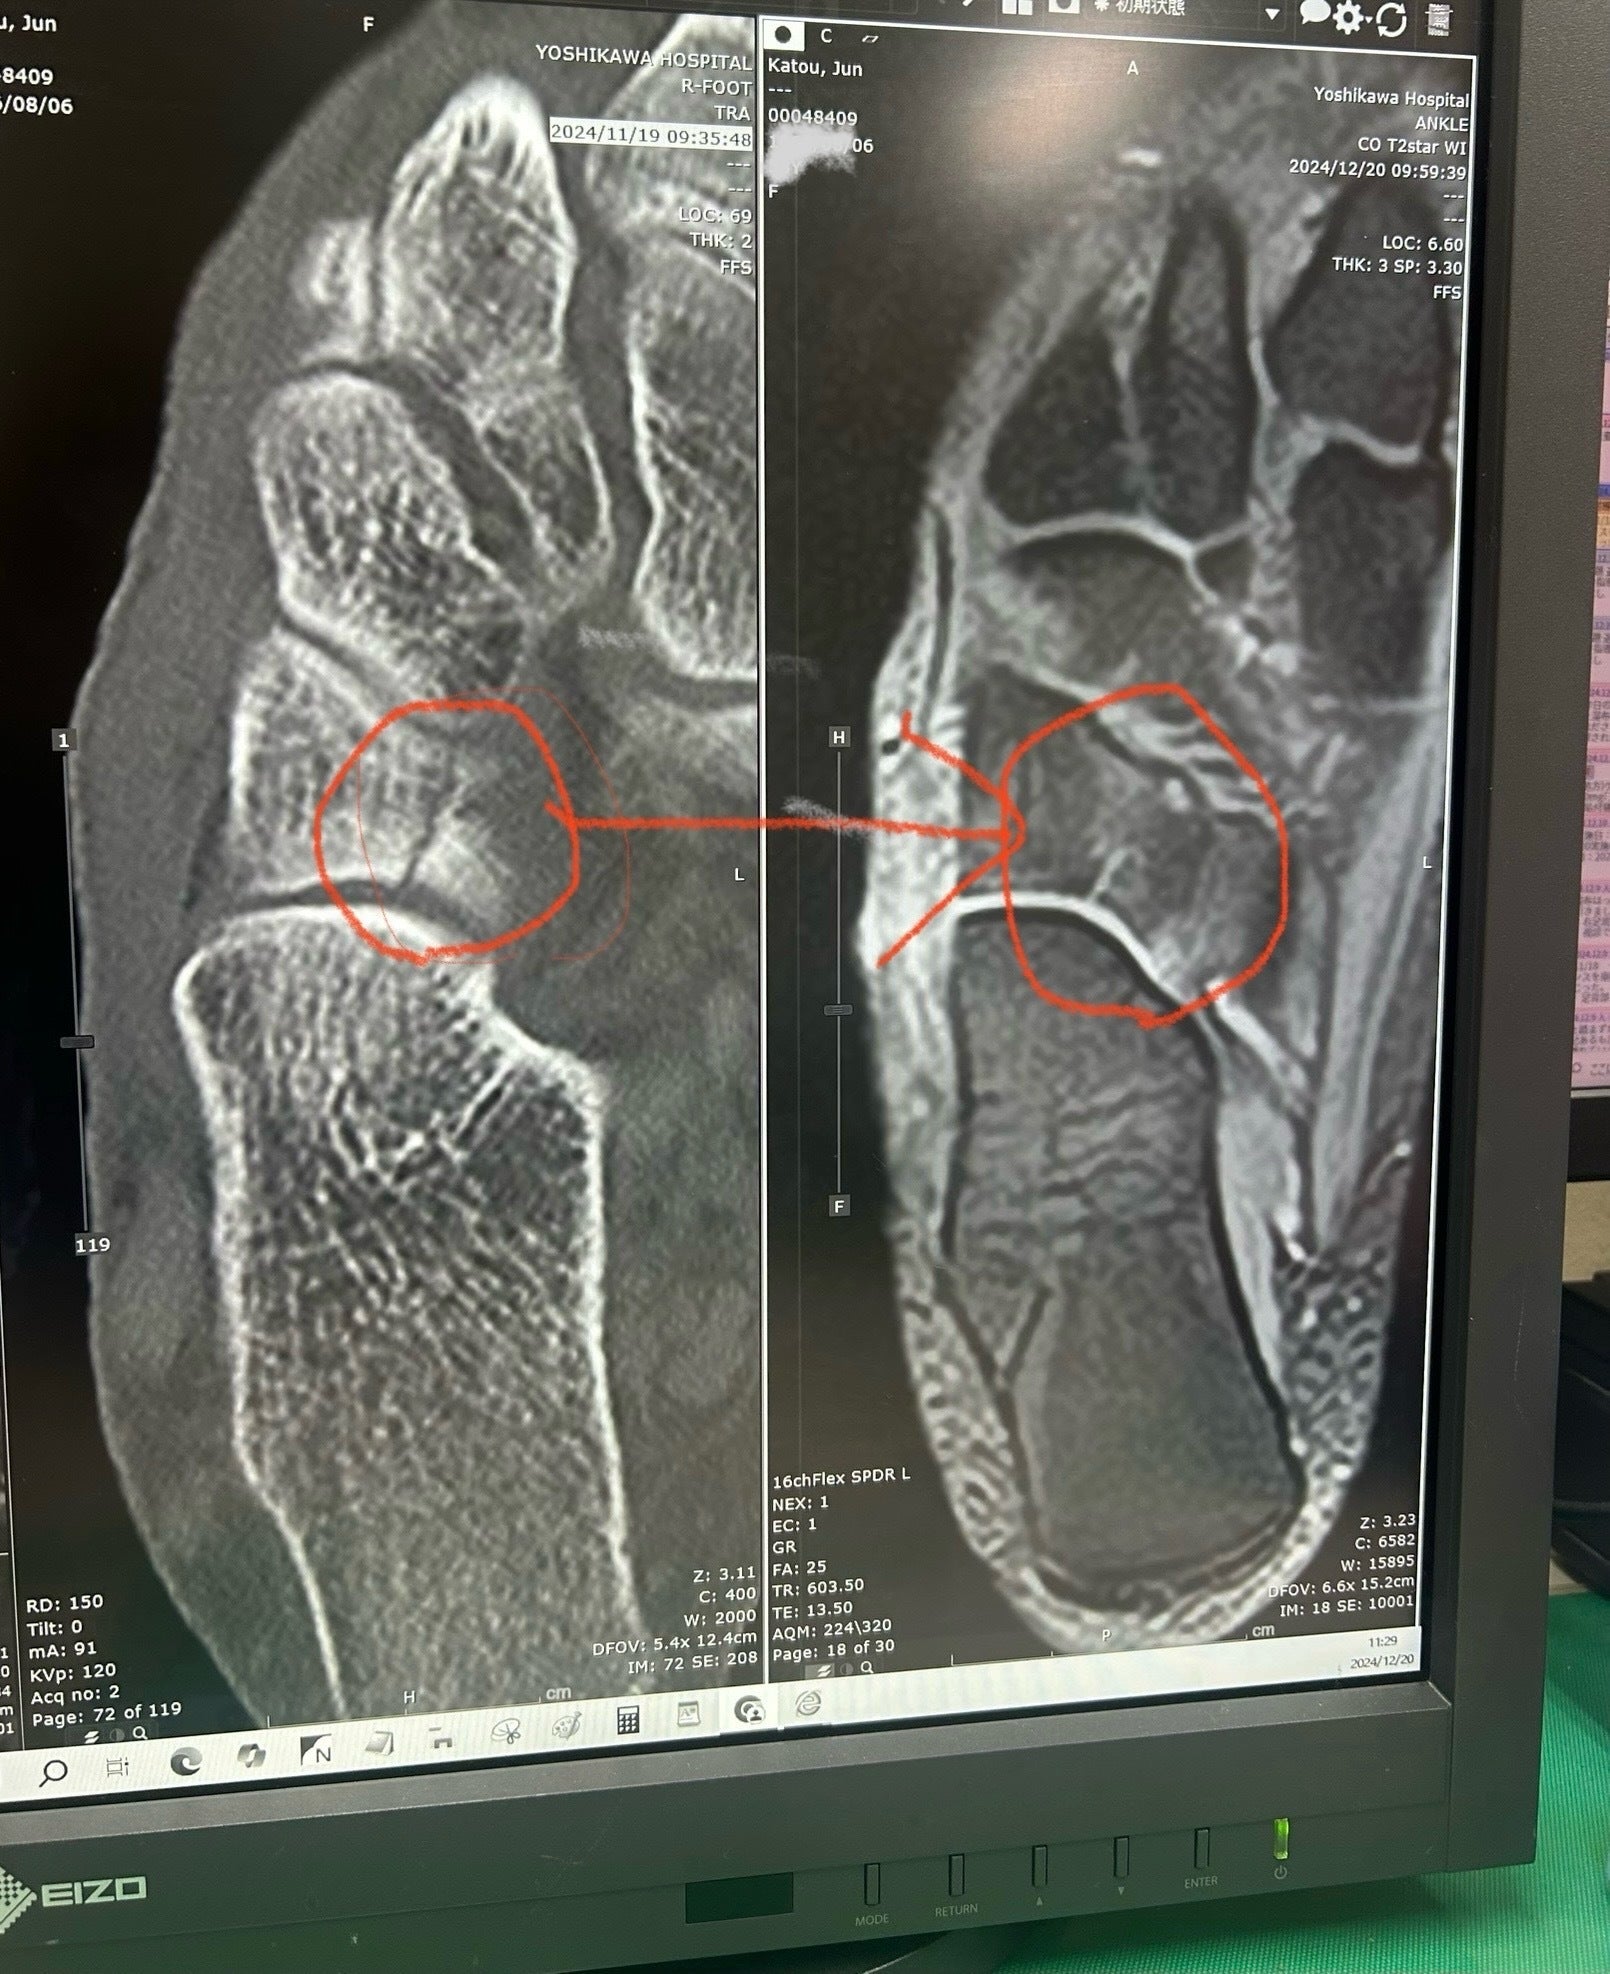

突然の怪我と、治癒力の可能性を確信

2024年11月18日京都での活動を終える準備中に右足を骨折

全治3ヶ月と診断されましたが、1週間の自宅療養と2週間の入院生活を経て、独自の治癒力を活かし、自己治癒とリハビリに励みました。医師も驚く脅威の回復力

1ヶ月後の検診で2/3の骨の接合。回復を達成し、医師を驚かせました。こ

の経験を通じて、自己治癒力の可能性を改めて実感し、今後の施術に活かしています。 2024年12月9日退院